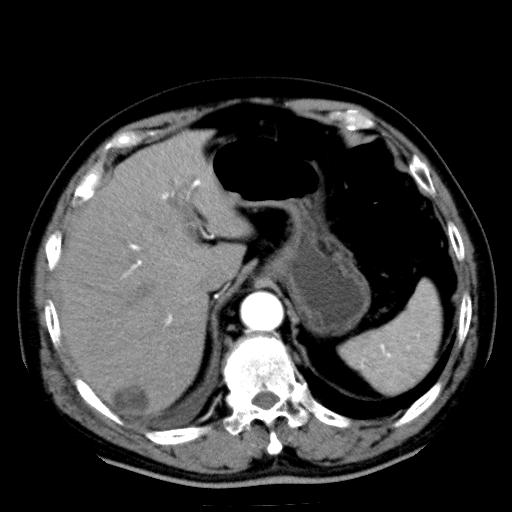

以下是引用zhctwbh在2008-8-23 14:20:00的发言:[br]囊肿合并出血

以下是引用zjb在2008-8-23 16:41:00的发言:[br]囊肿并出血可能性大。